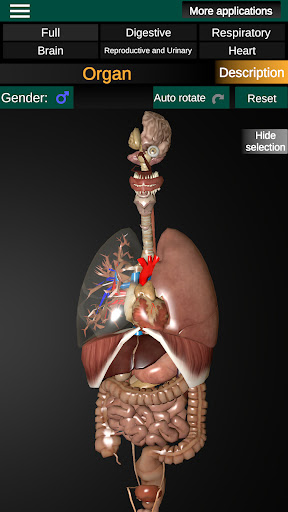

Показує 3D анатомічну модель основні органи людського тіла та опис кожного з них.

Що в додатку?

* Травна система, включаючи шлунок, тонку кишку, товсту кишку та анімацію цієї системи.

* Дихальна система, яка включає трахею, бронхи, легені та анімацію цієї системи.

* Легкий доступ і навігація (масштабування, 3D-обертання).